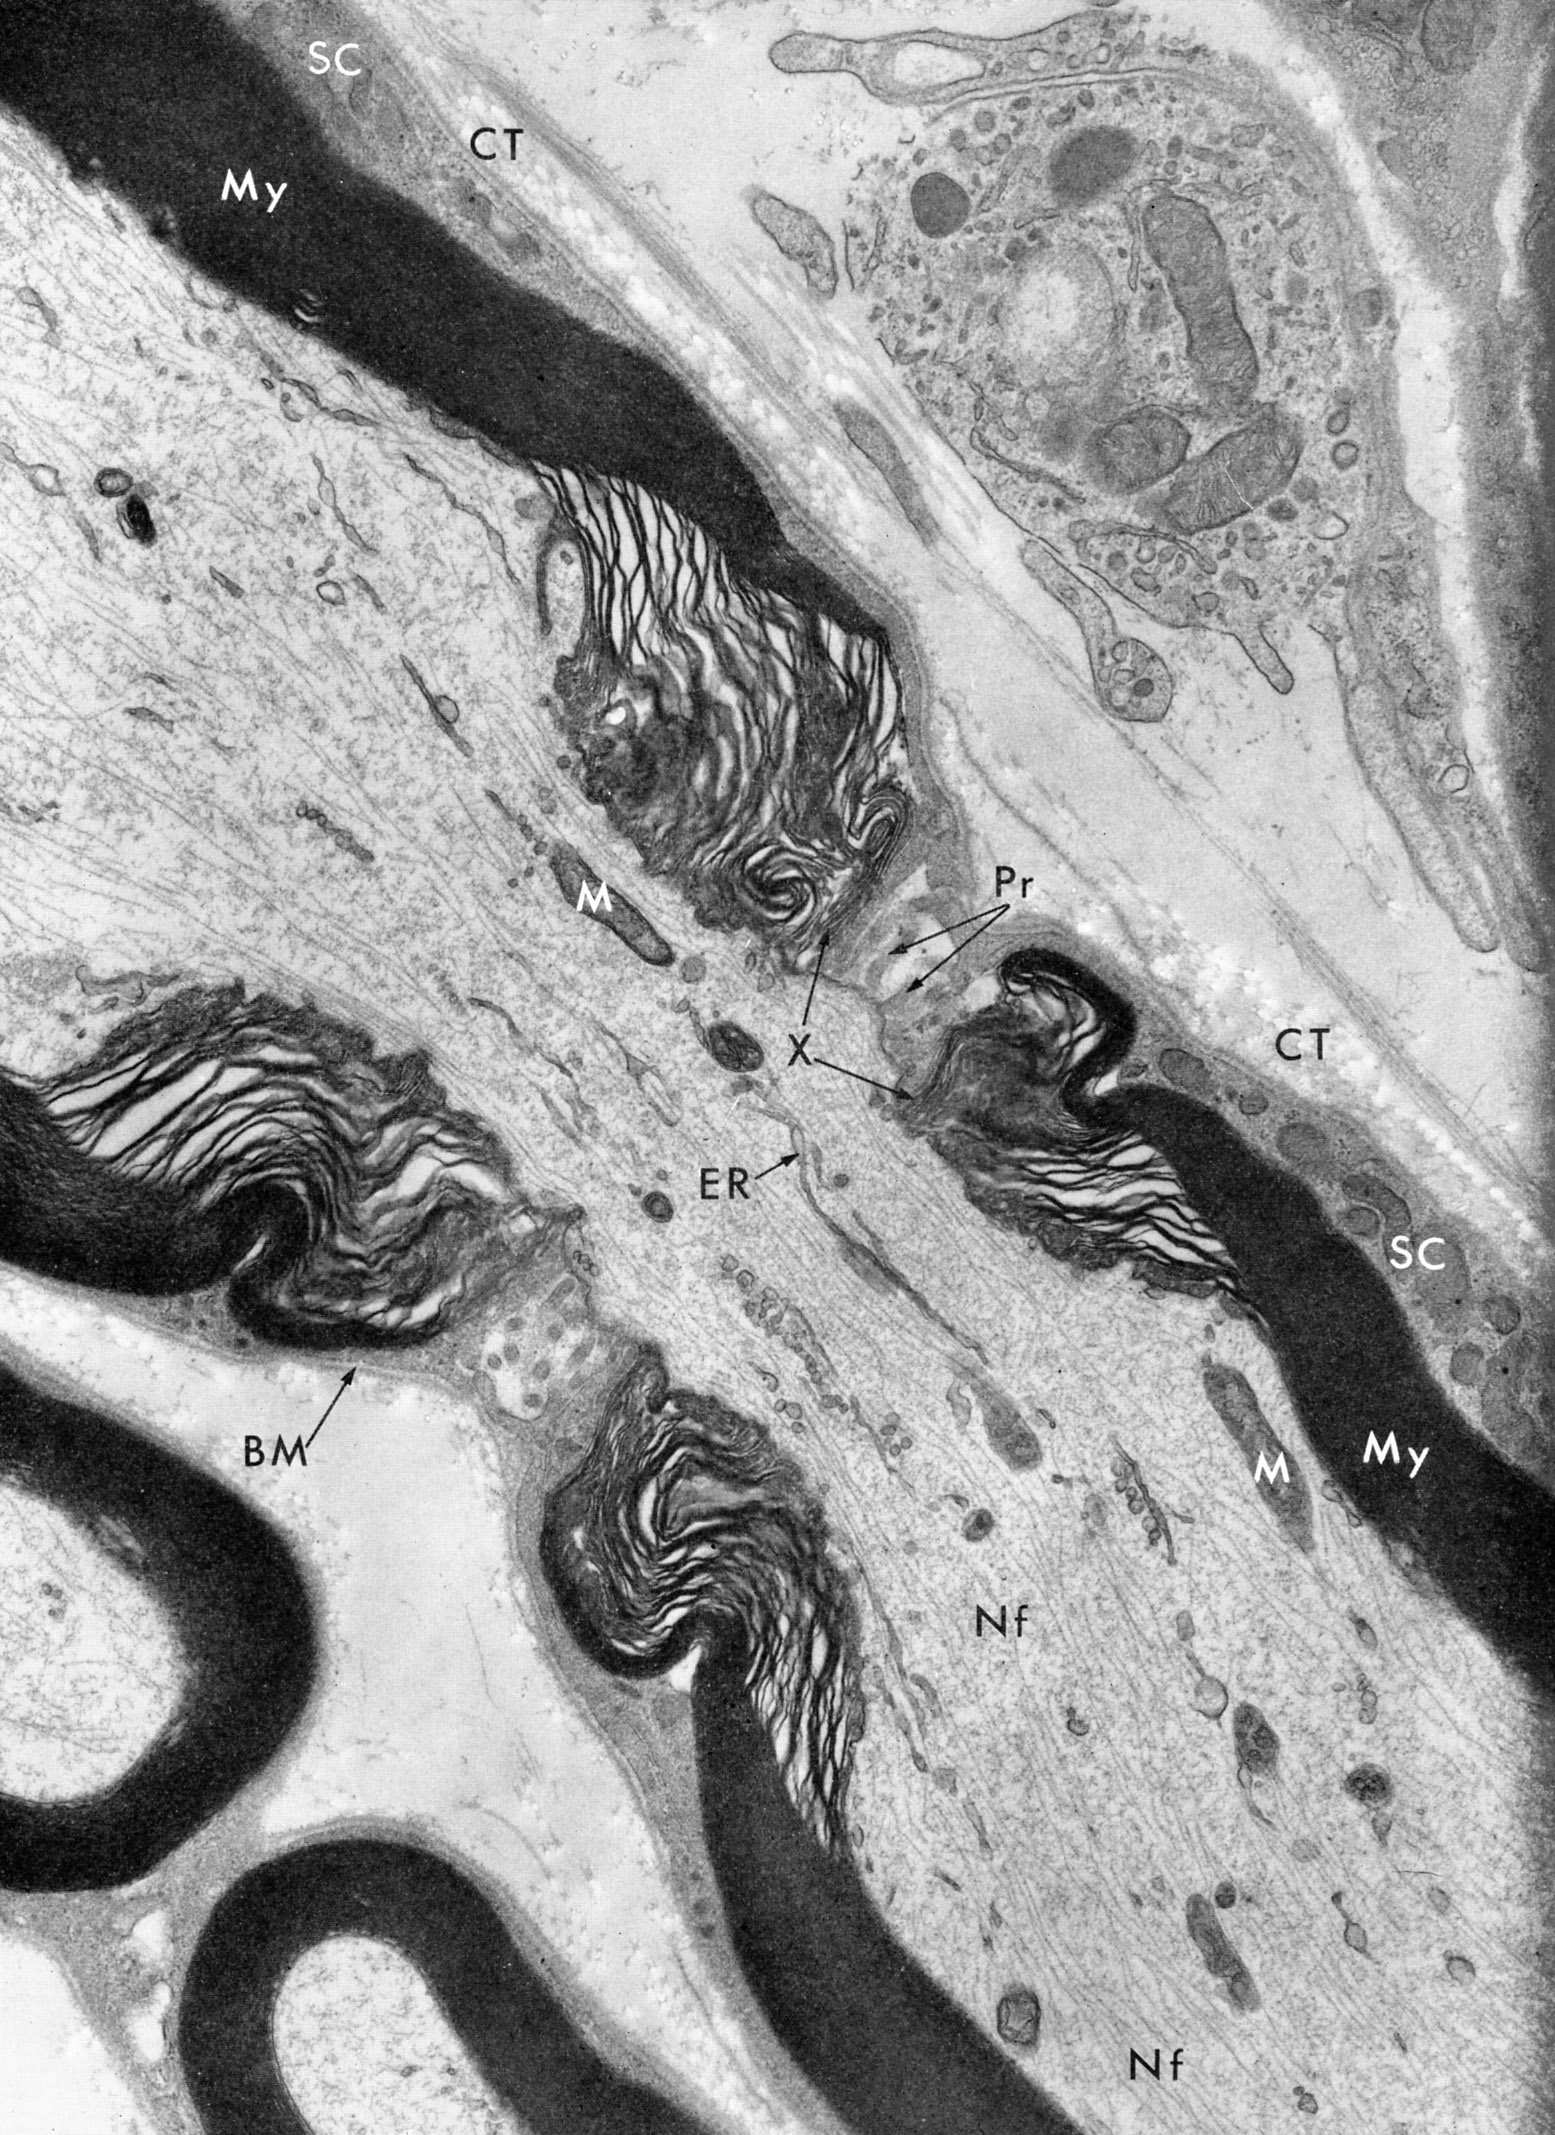

Roneo 9 p 6, on parle des différences de myélinisation de SNC et snP

Donc c'est marqué qu'il peut y avoir du cytoplasme qui persiste dans l enroulement (oligodendrocytes) pour une myélinisation du SN central (mes phrases sont reformulées

)Est ce que ça veut dire qu'au niveau du SNP, il n y a plus de cytoplasme dans la C de Schwann quand le mesaxone s'est enroulé ?

De même il est marqué que les noeuds de ranvier ne sont pas recouvert par les oligodendrocytes. Il persiste donc un espace extra cellulaire important (axone nu)

Ici la différence est bien au niveau de l importance de l'espace extra cellulaire ? Car dans les fibres myélinisés du snP il y a aussi des noeuds de ranvier donc un EEC non ?